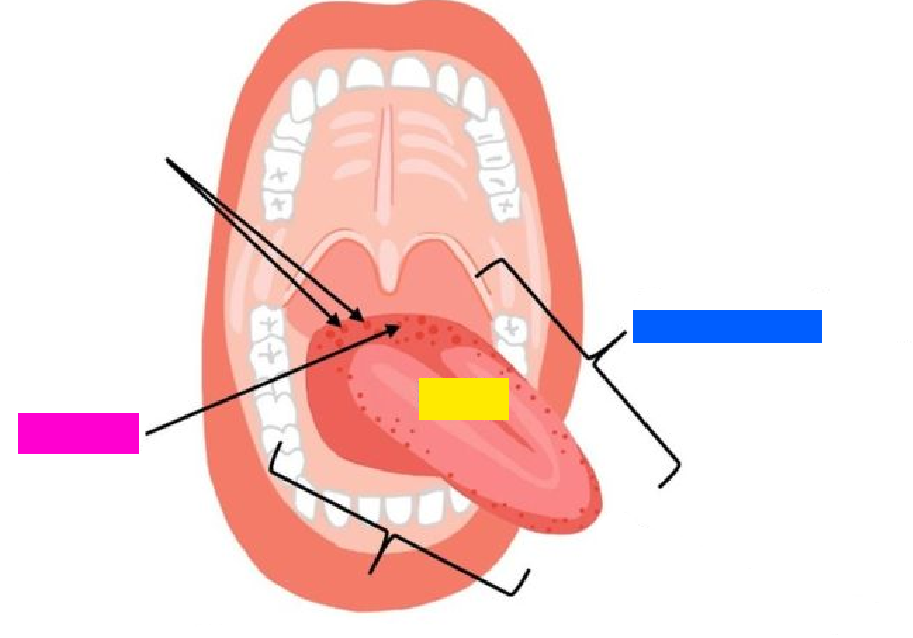

green highlight

Dorsum of tongue

blue box

Body of tongue

yellow box (referencing a section of the tongue)

Root of tongue

pink box

Papillae

(general term)

Lingual frenulum

Openings of submandibular ducts